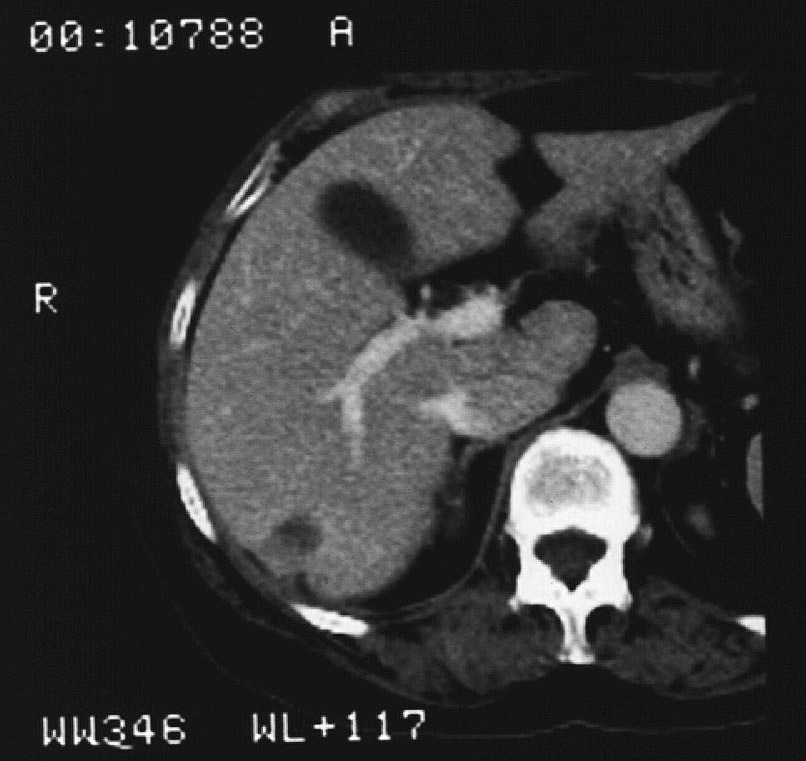

The effectiveness of the RF ablation is usually controlled by PET-CT examination, properly adjusted MR/CT protocols or with contrast enhanced US examination (figure 17.)

Image

Figure 17. – Control CT after liver RF ablation